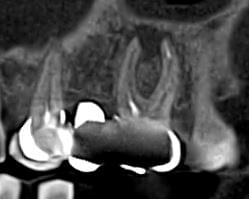

Успішна імплантація починається з бездоганної діагностики. Томограф PLANMECA забезпечує

зображення в реальному масштабі 1:1 без геометричних спотворень, що критично важливо для

вибору розміру та позиції імплантату.

Ми економимо ваш час, надаючи повний пакет передопераційної підготовки:

Детальна розмітка: промальовування нижньощелепного каналу, візуалізація синусів та

ментальних отворів.

Точні виміри: визначення висоти та ширини альвеолярного гребеня, а також оцінка щільності

кісткової тканини в зоні майбутньої операції.

Всі дослідження миттєво доступні у вашій персональній папці на нашому захищеному сервері —

ви можете відкрити їх на будь-якому комп’ютері для демонстрації пацієнту або планування

операції.